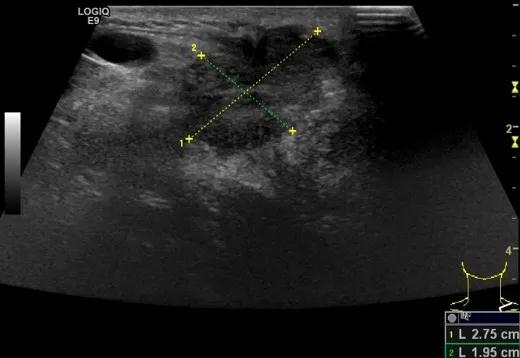

第二例是食管癌患者,术后半年余锁骨上固定淋巴结可触及肿大,疼痛非常明显,系统治疗后无缓解,患者希望通过局部处理缓解症状。造影显示强化信号明显,结节部分区域坏死,故主要针对强化区域从后向前的逐层的消融,皮下进行液体隔离减少烫伤。热消融后影像显示血流增强消失,弹性、硬度增高,一个月后复查显示充盈缺损,完全消融,疗效远超预期。

(病例2图例)